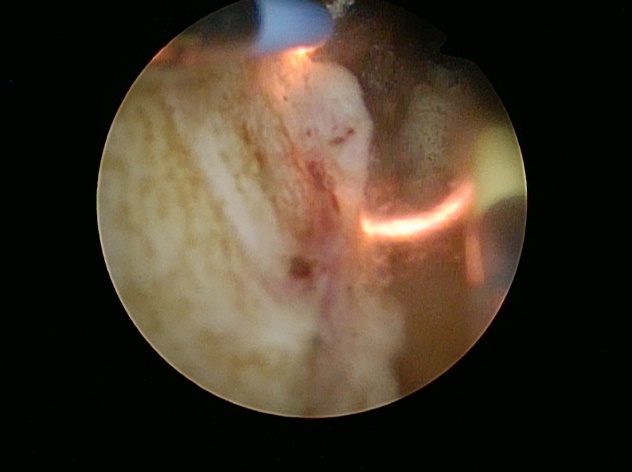

実際の切除中のループ